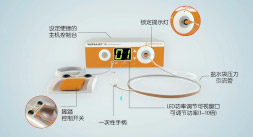

principle and development of water knife technology水刀技术通过独有组织细胞分离技术精准定位大汗腺,由发丝孔径大小的喷嘴喷射超高音速可调控的高压水流,系统采用了文丘里效应,通过无菌生理盐水水流粉碎、回吸异常大汗腺,同步实现安全便捷,术后创口自然美观,30分钟左右快速祛臭。

30 minutes comfort experience术前进行专业大汗腺毛囊检测,进行病理分析,根据病症的不同类型,严重程度,个人腋下皮肤基础条件制定出不同的祛臭方案。

- 压力调控

Break away from traditional treatment根据患者腋下的弧度选择适合患者最佳角度的手柄刀头量身定制祛臭专属方案。